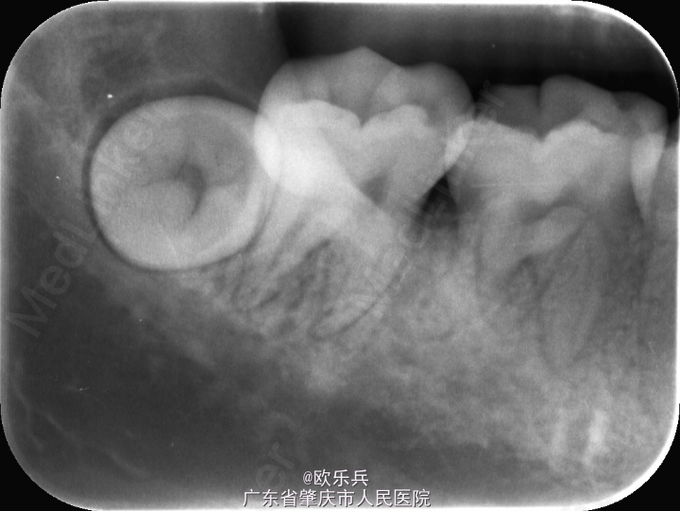

智齿颊向阻生

男,28岁,拍片发现右下智齿,要求拔除

检查右下8未萌,牙龈健康,无明显异常

48颊向阻生齿,局麻下翻瓣,去骨,分冠,挺出,缝合

颊向阻生齿,选择快机分压法比较好